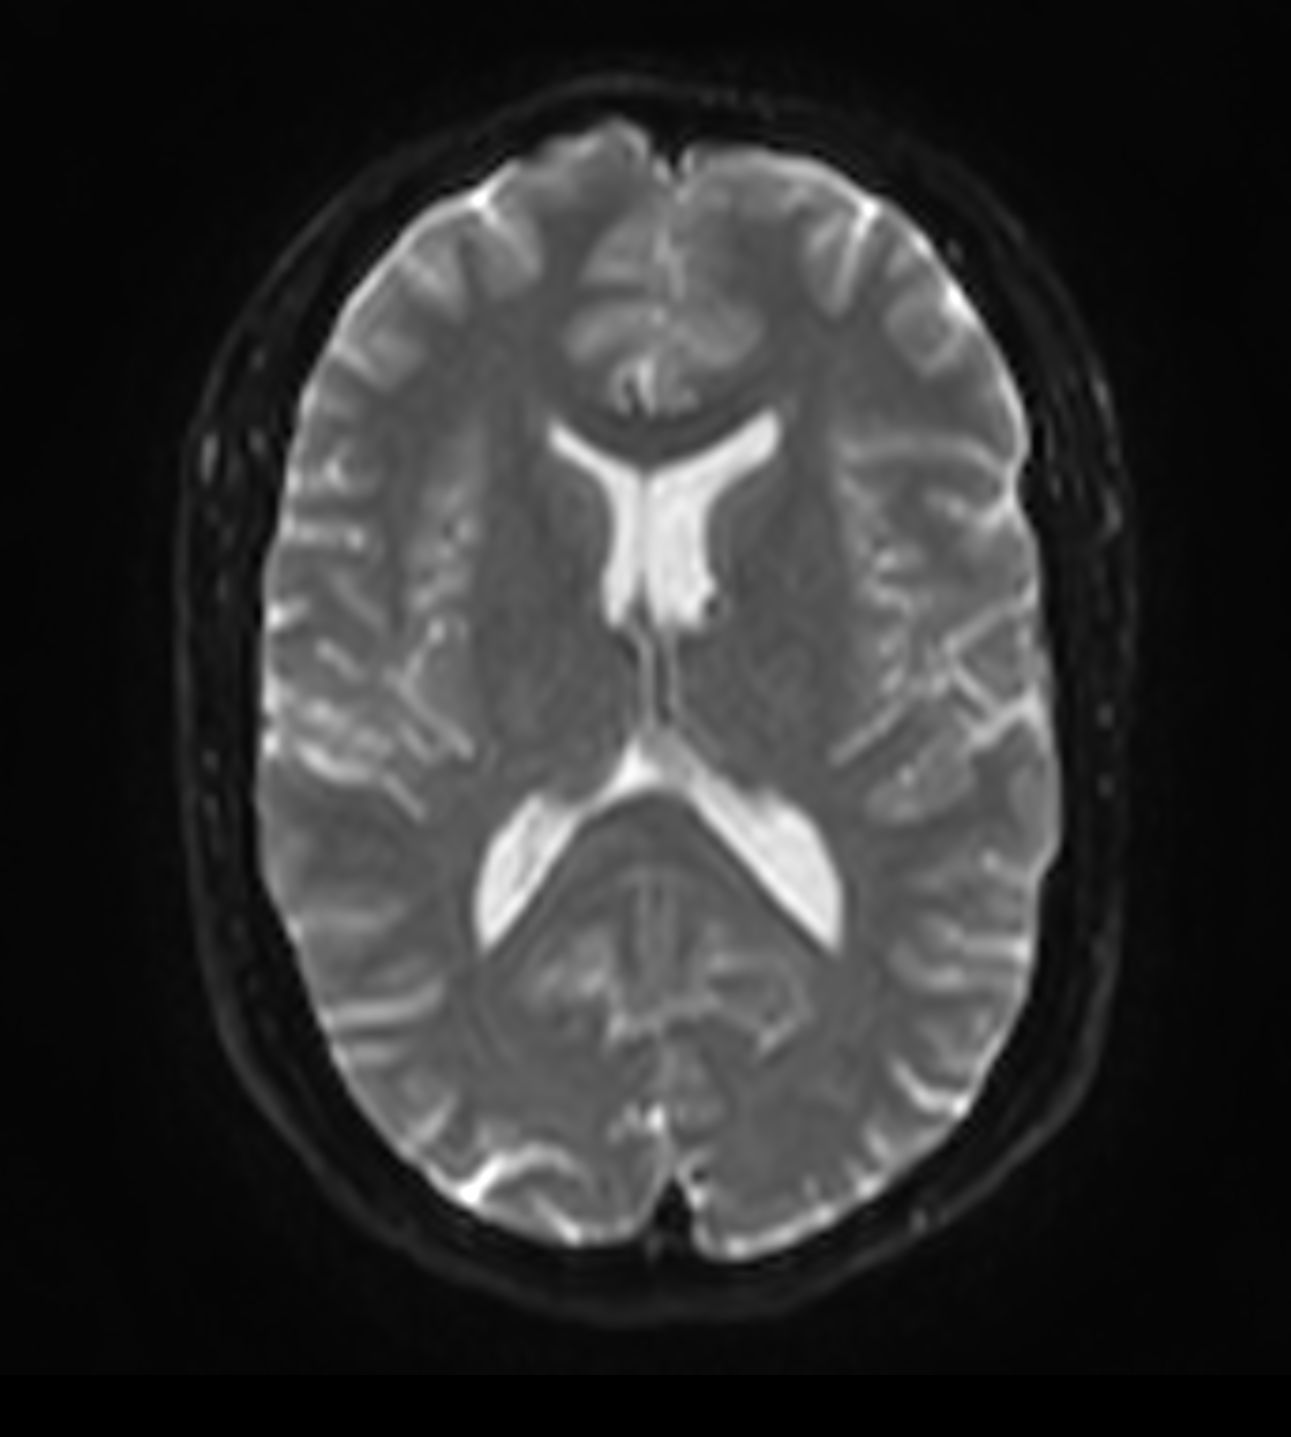

Alzheimer’s Disease Anti-Amyloid Immunotherapies (ARIA) 1.5T

Amyloid clearing medication, such as Aduhelm (Aducanumab) and Leqembi (Lecanemab) have been cleared by the FDA in 2022/2023, to slow down cognitive decline in early-stage Alzheimer’s disease. ASNR-recommendations for AD therapeutic imaging were published in 2022 for eligibility assessment as well as for monitoring for amyloid-related imaging abnormalities. This ExamCard includes ASNR-recommended consensus protocols for imaging of Alzheimer’s Disease Anti-Amyloid Immunotherapies (ARIA). (Cogswell et al., AJNR 2022,43(9)E19-E35;DOI: https://doi.org/10.3174/ajnr.A7586))